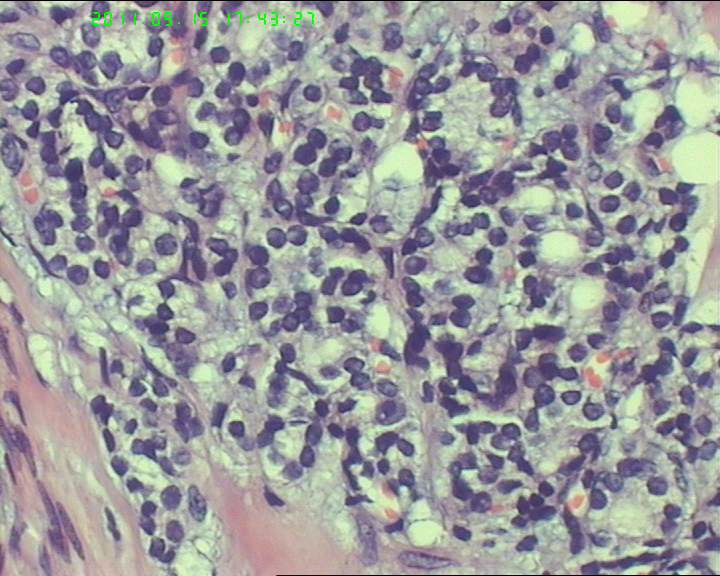

38岁女性甲状腺,腺瘤?滤泡癌?

甲状腺右下极一肿物,3*3大小,切面灰红实性质韧,可见部分包膜,一侧可见一空腔,未见内容物。

38岁女性甲状腺,腺瘤?滤泡癌?图4

名称:图4

描述:20110915-4.jpg.jpg

够不够滤泡癌,要找有没有浸润。网友们,这么多图片,有包膜浸润吗(哪几张是包膜)?图12、14又是什么?

如找不到明确的胞膜,血管浸润和正常甲状腺组织破坏,最好诊断非典型腺瘤.

非典型腺瘤,没有看到明显的血管浸润及包膜浸润